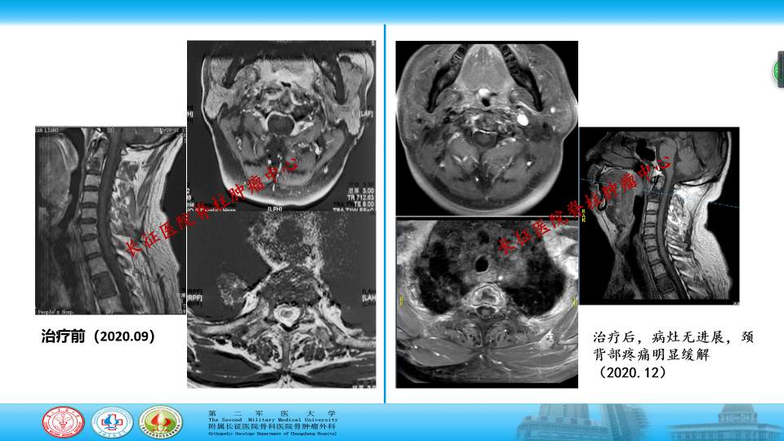

患者治疗三个月后发现肺部病灶明显缩小,脊柱转移病灶稳定。颈肩部疼痛治疗前为剧烈痛疼,影响睡眠,狄诺赛麦使用一次后,局部疼痛即明确缓解。

经保守治疗三个月后,该患者脊柱转移癌目前控制稳定,无神经压迫,无脊柱不稳,疼痛显著缓解,生活完全自理。